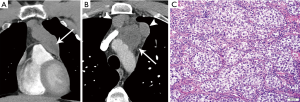

On imaging, the mass of PMLBCL is located in the thymic region (Figure 9), often large and bulky, and may invade the pericardium, pleura, or lungs, and involve supraclavicular and cervical lymph nodes (43). The aggressive nature of PMLBCL is reflected in its propensity to cause superior vena cava syndrome (43). Of note, involvement of other nodal regions or bone marrow involvement would preclude this diagnosis and rather indicate DLBCL with secondary mediastinal involvement (43). Pleural and pericardial effusions can occur, seen in approximately one third of patients (3).

The histological diagnosis is characterized by sheets or clusters of large malignant lymphocytes within dense fibrosis. Tumor cells are diffusely positive for CD20 and PAX-5 and have a high proliferation rate. The differential diagnosis also includes HL due to presence of fibrosis and the occasional Reed-Sternberg cells. However, PMBL lacks the classical inflammatory infiltrate seen in HL.

Mediastinal seminomatous germ cell tumors are the most common single histology primary mediastinal germ cell tumors. Seminomatous GCTs occur almost exclusively in men, and in women are called dysgerminomas. The majority occur in young men 20–40 years of age (3). Beta-hCG is increased in approximately one third of patients, and LDH may also be elevated (3).

On imaging, these masses are usually large and homogeneous in appearance, with mild enhancement on contrast-enhanced CT (9) (Figure 11). However, they may less commonly also have multiloculated cystic components (3). On MRI, seminomas are T2 hypointense and septae enhance. Metastases are reported in 40% (3), and extrapulmonary metastases confer poor prognosis.

On imaging, these appear as aggressive, heterogeneous soft tissue masses in the anterior mediastinum, often large and locally invasive. They are non-uniform in attenuation secondary to central areas of hemorrhage and necrosis, and peripheral areas of nodular enhancement (9). On MRI, hemorrhagic foci appear T1 hyperintense. Signs of local invasion include pleural or pericardial fluid, thickening, or nodularity, lymphadenopathy, or direct pulmonary parenchymal extension.